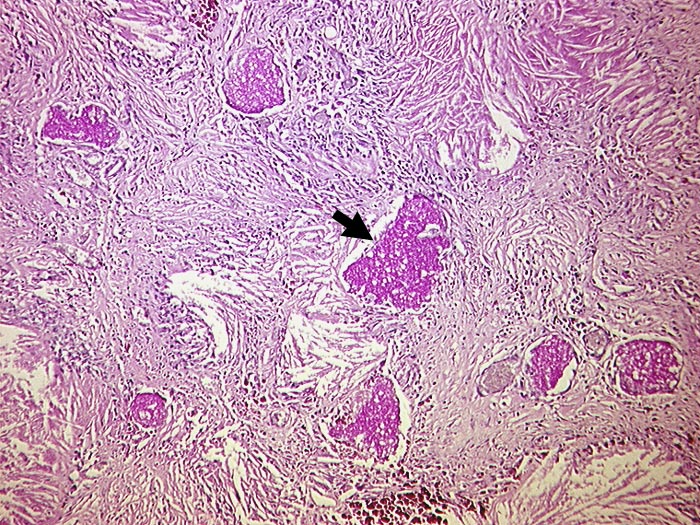

AP/ Pneumocystis carinii Pneumonie

Pneumocystis carinii Pneumonie

Lunge

Morphologie